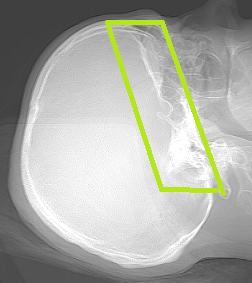

ÇEKİLECEK ALAN: Çekeceğimiz alan anteroir klinoidlerden başlayıp posterior klinoidler ve dorsum sella bitimine kadar olan bölgedir. Fov alanımızı ne kadar kısık ayarlarsak görüntümüz o kadar büyük gelecektir.

GÖRÜNEN YAPILAR: Hipofiz bezi , Sella tursika , Klinoidler ...

ÖRNEK KESİT: Fotoğrafları büyütmek için üzerlerine tıklayınız.